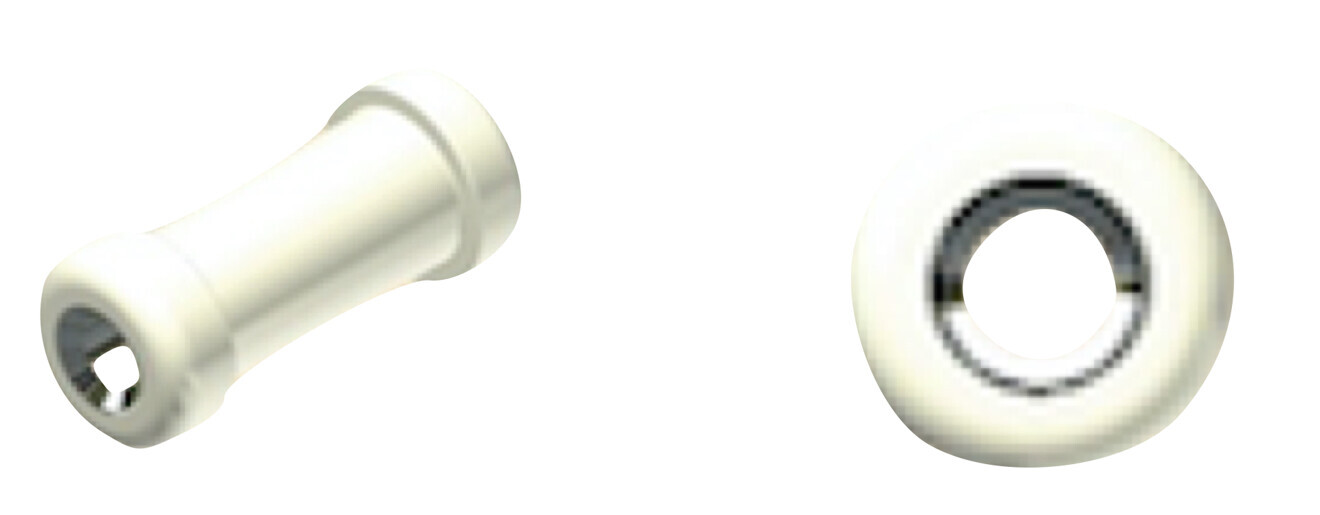

An alternative to TADs when impaction of the canines is less severe is the combination of aligners with an auxiliary called the Mini-Tube Appliance (MTA; Osstem Orthodontics). This useful auxiliary works like a conventional tube, but is covered with white resin to improve the aesthetics and has a silver-covered metallic slot (0.018 in. in diameter; Figs. 1 & 2). The advantage of these auxiliaries over a conventional sectional bracket system are their greater aesthetics, small size, ease of cleaning and, in particular, reduced friction thanks to the silver coating.

Fig. 1